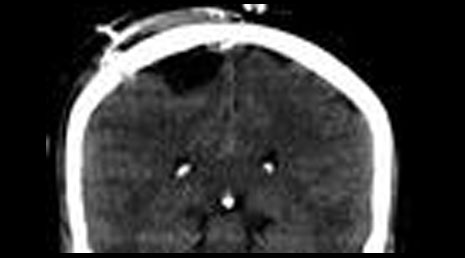

25. Cranial gunshot.